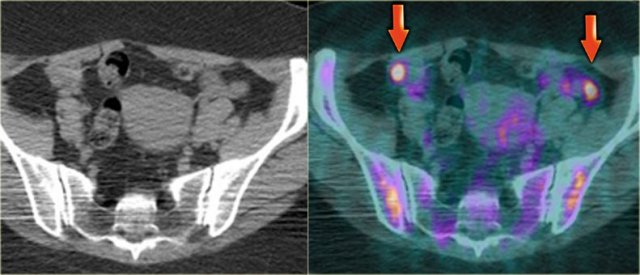

Cystic metastases to the ovaries

While metastases to the ovary are most commonly solid - such as for example Krukenbergs metastases - cystic ovarian metastases do occur.

The CT image shows complex cystic masses in both ovaries.

While a serous cystadenocarcinoma may very well be bilateral, they are more often unilocular than multilocular.

Barely visible is part of a circumferential colorectal cancer (blue arrow).

Clearly visible are cystic implants on the peritoneal reflection (red arrow). These were cystic ovarian metastases of a colorectal cancer. This is an uncommon finding.